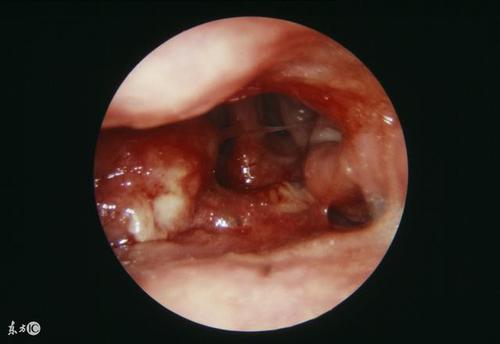

鼻咽癌早期内镜图片

鼻咽癌鼻咽镜图片

鼻咽癌菜花状图片